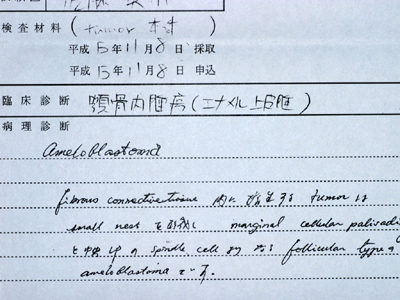

歯肉の変化を待つ、見逃さない

深いポケットを有する重度歯周病において、術後疼痛や冷水痛などの不快症状がなく良好な治癒に導きそれを再発させない秘訣は、ルートプレーニンングの開始時期にあります。『歯肉がブラッシングによって大きく変化したときに』『ポケット底から歯肉縁までの歯石を一気に』取り去って滑沢な根面に仕上げるのです。

浮腫性の歯肉、全顎にわたりpd8〜10mm、著しい動揺がみられる重症例です。

(下顎前歯部歯肉に注目ください)

初診から7wブラッシング指導のみ。歯肉に変化はみられますが、あえてまだスケーリングはせずもう少し歯肉が変化するのを待ちます。

さらにその3w後。浮腫性の歯肉が乾いた感じに変化しました。歯肉が治ろうとするサインです!この時を見逃さず、ポケット底から縁上まで1歯につき1回でルートプレーニングをします。

1ヶ月後、プロービングデプスは2〜3mmに改善しました。

メインテナンス3年が経過しました。再発もみられず安定しています。